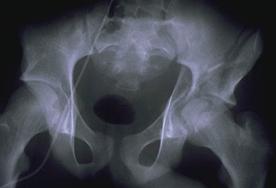

TRAUMATISMELE PELVIENE

Traumatism

pelvian Hemipelviectomie dreapta posttraumatica

Disjunctie de simfiza pubiana Disjunctie

de simfiza pubiana

Disjunctie sacro-iliaca stanga Disjunctie sacro-iliaca stanga. Aspect CT